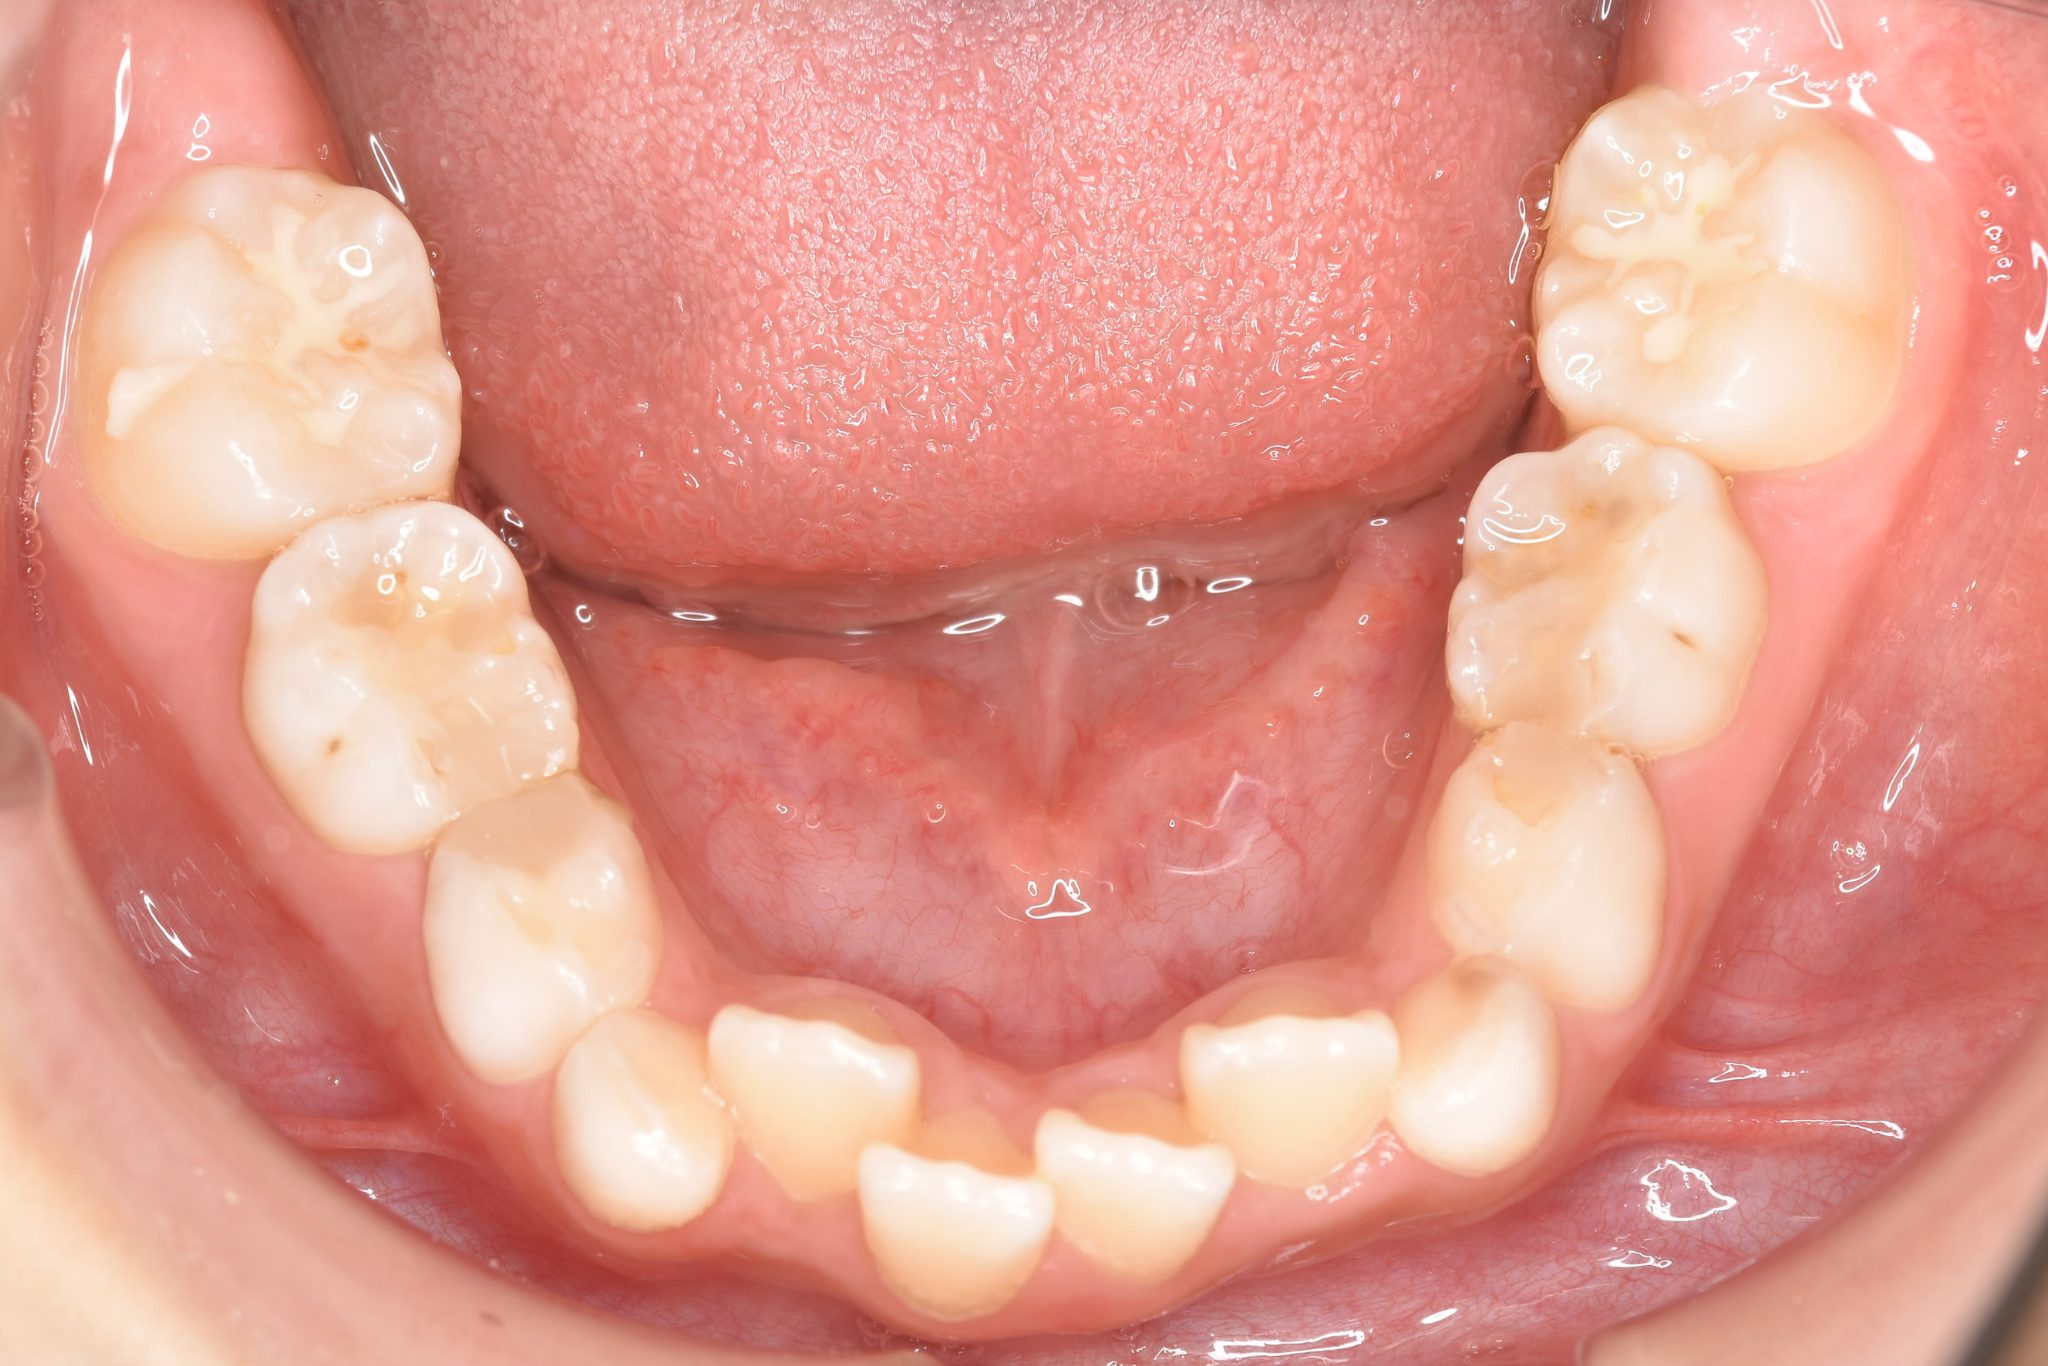

アフター

全顎ワイヤー矯正 症例_185

主訴 歯並び|横から生えている大人の歯

施術内容 小児矯正1期治療

治癒期間 4年間

費用 522,960円(税込)

リスク・副作用 違和感、不快感、痛み